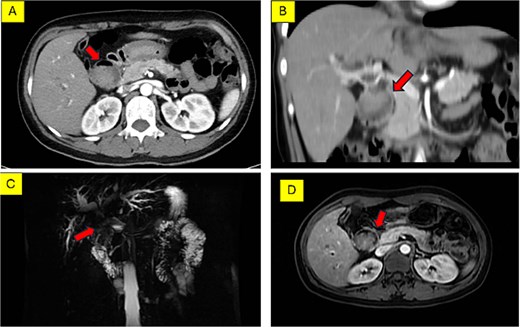

Abdominal ultrasound and CT showed a hilar mass causing biliary obstruction and pneumobilia, initially raising suspicion of hilar cholangiocarcinoma complicated by a fistula (Fig. 1A and B). However, MRCP suggested a duodenal tumor at the D1 – D2 junction invading the biliary tree (Fig. 1C and D). Esophagogastroduodenoscopy revealed a large diverticulum (30 mm) impacted with food debris at the D1-D2 junction, without visible intraluminal tumor. Consequently, Lemmel’s syndrome was considered the primary working diagnosis.

Preoperative imaging of the hilar lesion. (A) Axial MSCT scan showing the mass. (B) Coronal MSCT scan demonstrating the extent of the lesion. (C) 3D reconstruction of the biliary tree indicating the location of the tumor. (D) Axial MRI scan (T1-weighted) of the lesion.